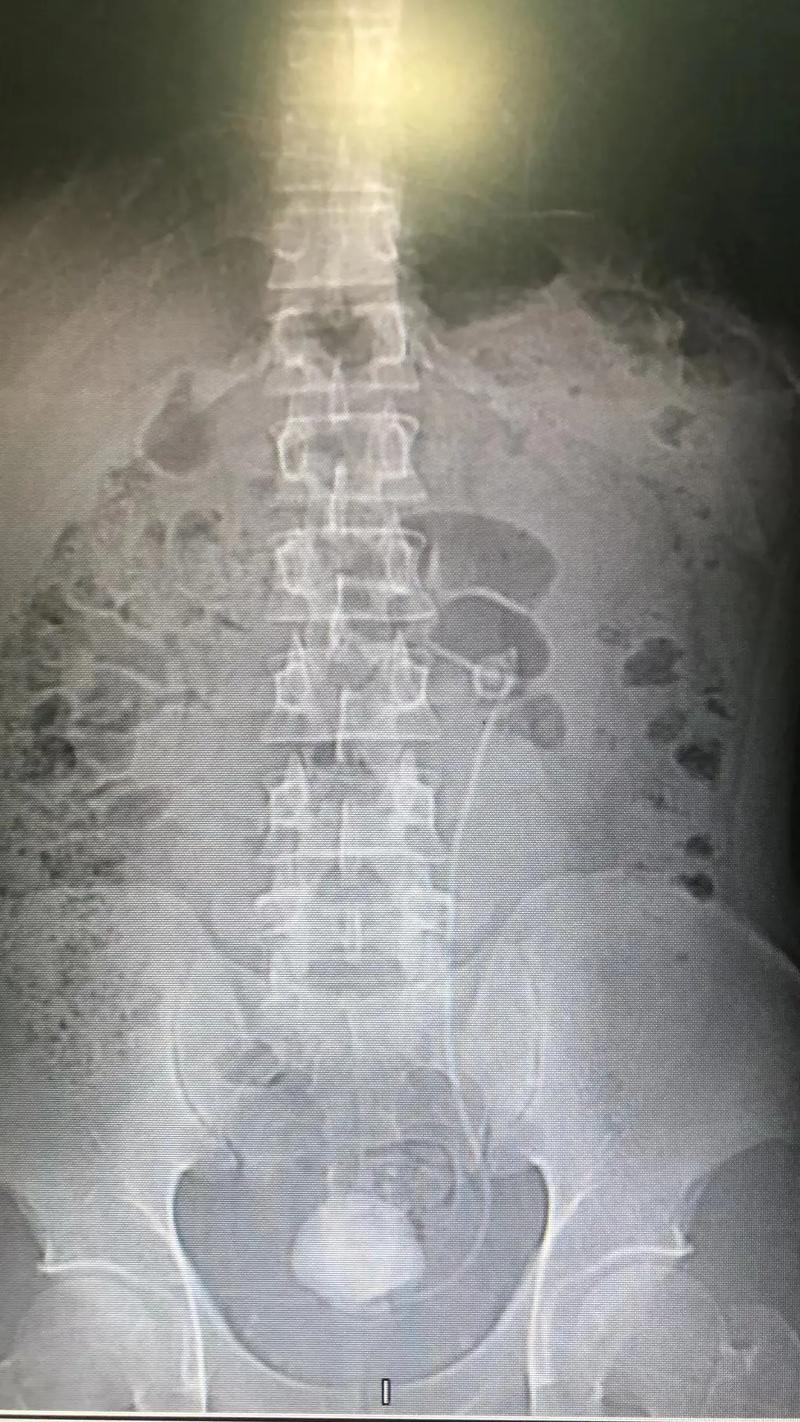

6、当结石卡在输尿管下段时,需根据结石大小位置及患者症状选择个体化治疗方案,具体措施如下1 就医检查明确病情首先需通过超声CT等影像学检查确认结石位置大小及是否存在肾积水等并发症医生会综合评估患者症状如疼痛程度血尿情况制定治疗方案例如,若结石直径小于06厘米且无严重梗阻,可能。

7、结石卡在输尿管下段时,可通过大量饮水调整饮食药物治疗体外冲击波碎石术ESWL或输尿管镜取石术等方式处理,具体需结合结石大小症状及医生建议选择合适方案具体如下大量饮水保持每日饮水量在20003000毫升以上,充足的水分摄入可稀释尿液,减少结石形成风险,同时通过增加尿量产生冲刷作用。

8、若结石卡在输尿管下段,需根据具体情况采取针对性治疗措施,核心原则是及时解除梗阻保护肾功能,并预防结石复发首先,需评估病情严重程度若结石卡顿时间较长,已引发输尿管扩张肾脏积水或感染如发热腰痛加剧,需立即就医此时肾脏功能可能受损,延迟治疗可能导致不可逆的肾损伤,甚至引发脓毒血症等危及生命的。

10、较大的结石碎片可以用取石钳取出,从而快速缓解输尿管的梗阻,并缓解患者的临床症状及时治疗的重要性如果结石长时间卡在输尿管下段,可能会导致输尿管积水和肾脏积水,进而可能损害患者的肾脏功能因此,一旦发现结石卡在输尿管下段,应及时就医并接受专业治疗,以避免潜在的并发症。

12、结石卡在输尿管下段需及时就医,采取以下综合措施处理一优先选择输尿管镜碎石术输尿管下段空间狭窄,若结石直径超过6mm,单纯药物排石效果有限此时需通过输尿管镜碎石术如钬激光碎石直接击碎结石并取出,这是目前临床最常用的微创治疗方法该手术通过尿道插入内镜,精准定位结石后粉碎,具有创伤。

14、输尿管结石卡在下段,可能会导致严重的腰骶绞痛,有时还伴有恶心呕吐发热等症状一旦结石卡住,疼痛可能会减轻或消失这时,可采用辅助排石疗法,如服用排石药扩张输尿管药物以及缓解输尿管水肿药物,同时保持充足的水分摄入和适度运动抗生素的使用能预防肾积水的形成对于体积较大的结石,或。

15、回答病情分析 肾结石一般在06以下的是药物排石,常用的药物如肾石通颗粒,排石颗粒等大于06以上的是体外冲击波碎石,大于20以上的可以手术治疗 指导意见 建议患者到医院给予彩超检查,明确结石大小后给予选择合适的治疗方案。